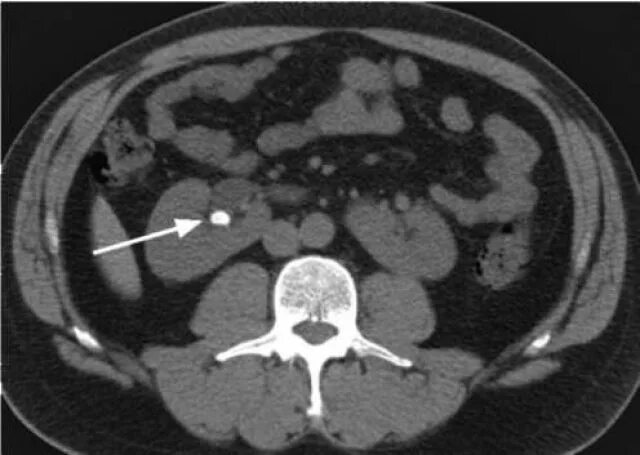

Заболевание кт